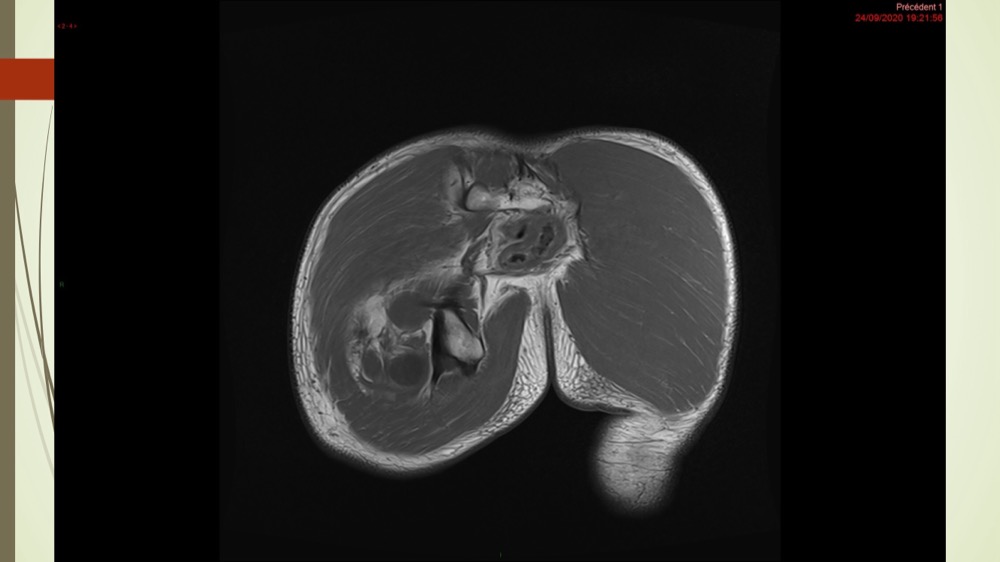

Coxalgie traînante

Kévin Mahé 29/06/2022